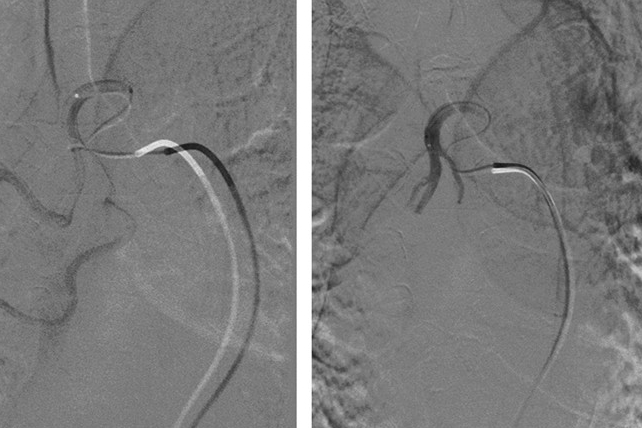

3月16日,台州市青年消化医师论坛暨消化道早癌病例讨论会在我院2号楼五楼多功能厅举行。多位消化科专家及优秀青年医师纷纷来到玉环,共同探讨消化道早癌领域新进展。会上,我院常务副院长江松福代表医院致辞,欢迎各位专家与优秀人才的到来,并预祝论坛取得圆满成果。海军军医大学附属长海医院辛磊教授作《青年消化医师培养》,全面介绍了国内消化内镜发展与培训现状。他表示目前消化内镜培训任务迫切,建议结合国外消化内镜医...